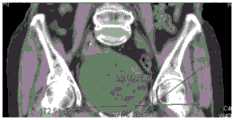

The existing preoperative planning is to design and manufacture an individual template according to a three-dimensional digital model of CT data of a patient and characteristic bone mark points, integrate a reference area of a real bone structure of the patient into the template, and is equivalent to marking the template, so that the template and the bone structure can be accurately identified and registered. Two key parameters, anatomical abduction Angle (AI) and anatomical Anteversion Angle (AA), refer to the angle between the acetabular axis and the long axis of the body and the angle between the projection of the acetabular axis onto the body cross-section and the transverse axis of the body, respectively. FIG. 1 is a CT image taken from the plantar portion of a patient for calculating the anteversion angle of the patient; fig. 2 is a CT image taken from the front of the patient for the measurement of the abduction angle of the patient. When the acetabular prosthesis is installed in the operation process, the acetabular prosthesis is installed by using the corresponding acetabular angle installation handle and matching with abundant operation experience of doctors according to the figures 3 and 4.

Fig. 1.Ct image is used to obtain the patient's anteversion angle.

Fig. 2.Ct image is used to obtain the valgus angle of a patient.